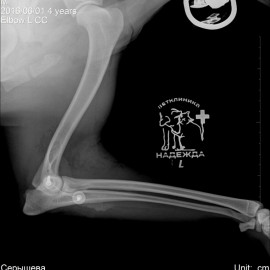

Обратились с жалобами на остро развившееся отсутствие опороспособности на левую переднюю лапу после прогулки. После исследований был поставлен диагноз: медиальный вывих левого локтевого сустава. Была проведена операция: остеосинтез левого локтевого сустава. Был установлен протез латеральной коллатеральной связки.

Снимки 2-3 после операции